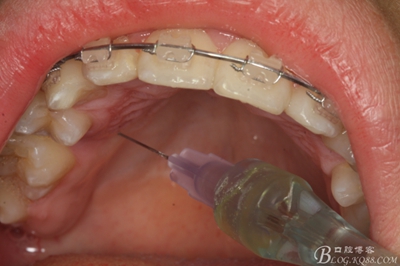

圖6.唇側局部無痛浸潤麻醉

圖7.腭側無痛浸潤麻醉